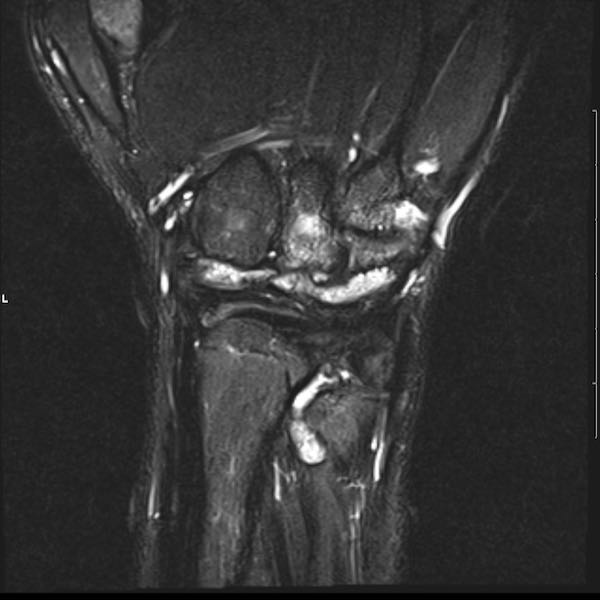

Tiếp tục xem hình ảnh MRI của bệnh nhân này.

Hình ảnh MRI:

Tràn dịch lan tỏa tất cả các khớp cổ tay.

Phù tủy xương lan tỏa tất cả các xương cổ tay.

Bào mòn xương, ví dụ tại xương thuyền, xương đầu và xương móc.

Phá hủy khe khớp và sụn khớp, rõ nhất tại khớp STT và CMC4/5.